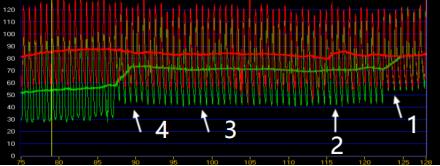

▲FFR测量数据

在心血管内科介入团队的紧密配合下,FFR检测仪器有条不紊地记录下患者血管内的血流情况。经过精准的数据测量,对前降支中段及中远段狭窄进行血流储备分数测定,测得数值0.84,对右冠脉近段及开口处狭窄进行血流储备分数测定,测得数值0.96-1.0,患者冠状动脉狭窄处血流储备分数测得值均大于0.80,综合患者病情及FFR结果,无需植入支架,药物保守治疗即可。